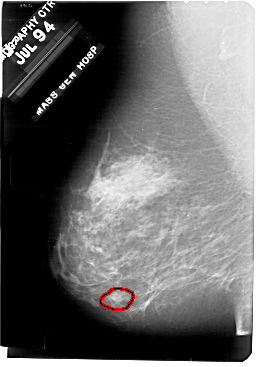

A_1707_1.LEFT_MLO

LEFT_MLO LINES 5491 PIXELS_PER_LINE 3856 BITS_PER_PIXEL 12 RESOLUTION 43.5 OVERLAY

FILE: A_1707_1.LEFT_MLO.OVERLAY

TOTAL_ABNORMALITIES 1

ABNORMALITY 1

LESION_TYPE CALCIFICATION TYPE PLEOMORPHIC DISTRIBUTION CLUSTERED

ASSESSMENT 4

SUBTLETY 1

PATHOLOGY BENIGN

TOTAL_OUTLINES 1

BOUNDARY